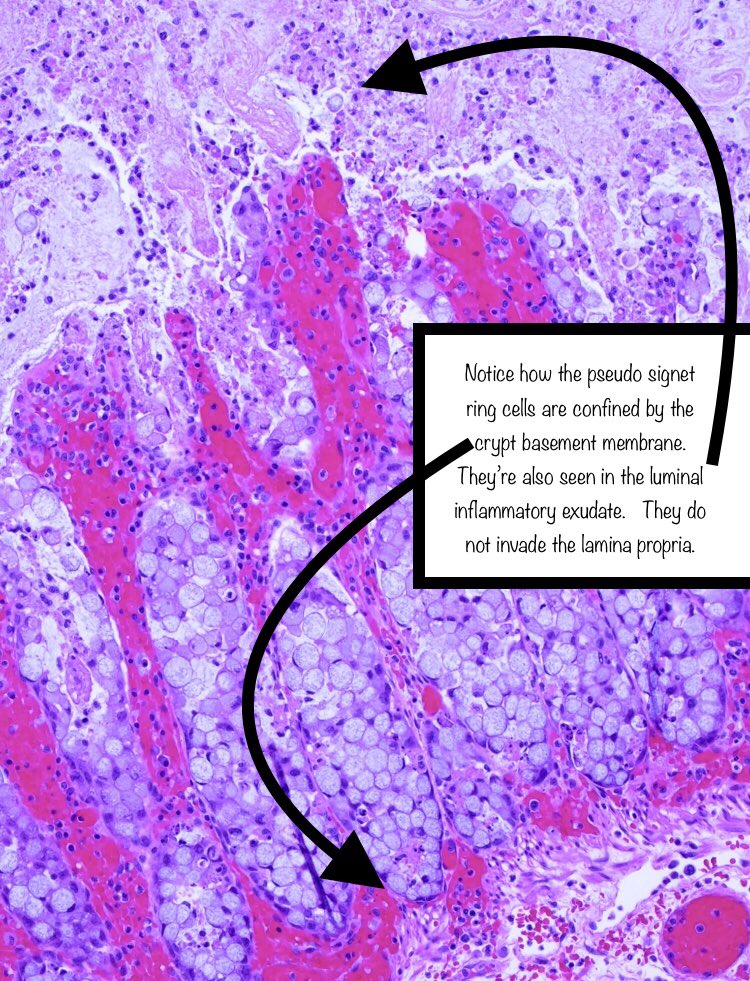

How do we differentiate benign signet ring cell change from signet ring adenocarcinoma?

Context is key: signet ring cell change may be seen in pseudomembranous colitis; also other ischemic and ulcerative conditions.

The cause of signet ring cell change isn’t completely understood. Apparently, mucosal inflammation and ischemia cause epithelial cells to slough and ‘round up’, resulting in signet ring-like morphology.